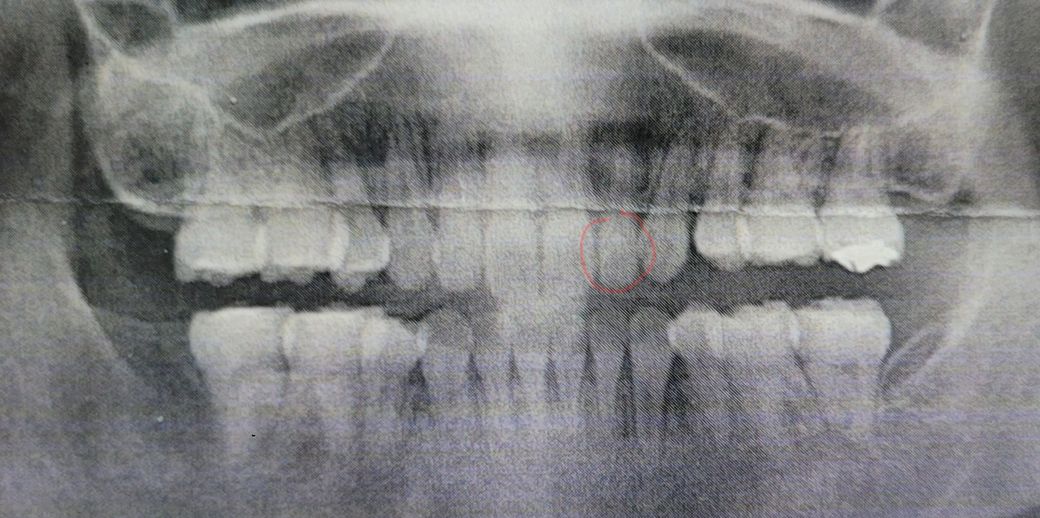

이 앞니가 살짝 불편한데 뿌리 염증일까요?

사진은 재교정 관련 상담받고 사진 인쇄해주신거 찍은거인데요 동그랗게 표시한 치아가 원래 몇달 전부터 좀 불편한 감이 있었는데 교정 상담 받고서 따로 거기서 충치나 다른말이 없으셔서 문제없는 줄 알았거는요.

근데 지금보니 저 치아 뿌리만 어둑한게 혹시 뿌리 염증인가 싶어서 질문글 올려봅니다. 따로 외상 입거나 큰 충치는 없었던 치아라서 당황스럽네요.

뿌리 염증이면 신경치료 해야겠죠..?

1. 파노라마 방사선 사진(큰사진)에서는 다양한 음영과 겹치는 구조때문에 왜곡이 발생하기도 합니다. 자세히 보기 위해서는 작은 방사선 사진(치근단방사선사진)을 찍어봐야 합니다.

2. 뿌리 염증이 맞고 불편감이 있다면 신경치료 해야 합니다.